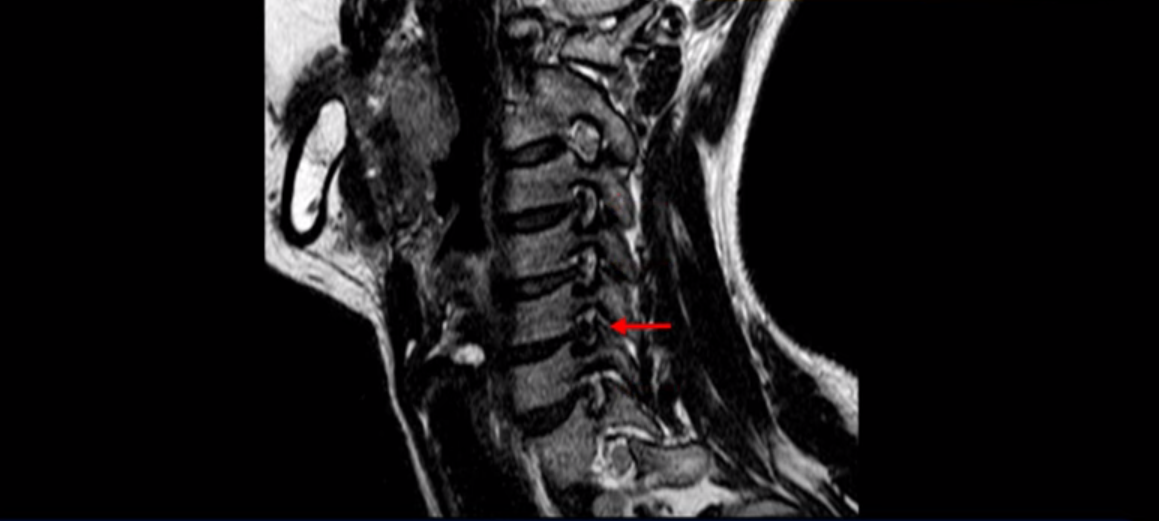

우선 이분 MRI를 보기 전에 이분 증상에 대해 말씀 드리면 오른쪽 팔저림과 방사통 및 어깨 통증이 있습니다. MRI를 보면 4번 5번에 디스크 파열이 보입니다.

밀려나온 디스크가 위로 타고 올라가 있는데 보시다시피 가운데로 밀려 나와 있습니다.

그래서 이게 오른쪽 통증의 원인일 수도 있고 아닐 수도 있습니다. 5번 6번은 왼쪽으로 밀려 나와있으니까 오른쪽 통증의 원인이 아닙니다.

그런데 이분 목을 보시면 여러 마디의 뼈가 퇴행이 진행되어 있습니다. 뼈가 깍두기처럼 각지고 예뻐야 하는데 끝이 조금씩 변형되어 뾰족하게 자라고 있습니다.

이런 게 협착을 일으킵니다. 그래서 우선 오른쪽 신경구멍 즉 추간공을 살펴보면 맨 위의 한마디를 빼고는 다 좁아져 있습니다.

특히 5번 6번 구멍이 가장 좁습니다. 이걸 협착이라고 합니다.

사실 여러 신경 구멍이 다 좁아져 있기 때문에 정확히 어느 마디가 방사통을 일으키는지 정확히 알기 어렵습니다. 그래서 만일 수술을 한다면 정확히 어느 마디가 진짜 원인인지 파악하지 못한 채 한다면 수술이 크게 실패할 수도 있습니다. 또한 이분처럼 여러 마디가 안 좋아서 수술한 마디의 위나 아래가 상태가 좋지 않으면 유합술 후 그 위나 아래에서 또다시 문제가 생기는 인접 분절 질환이 수술 후에 발생할 수도 있습니다. 이런 정도는 알아두는 게 좋습니다.